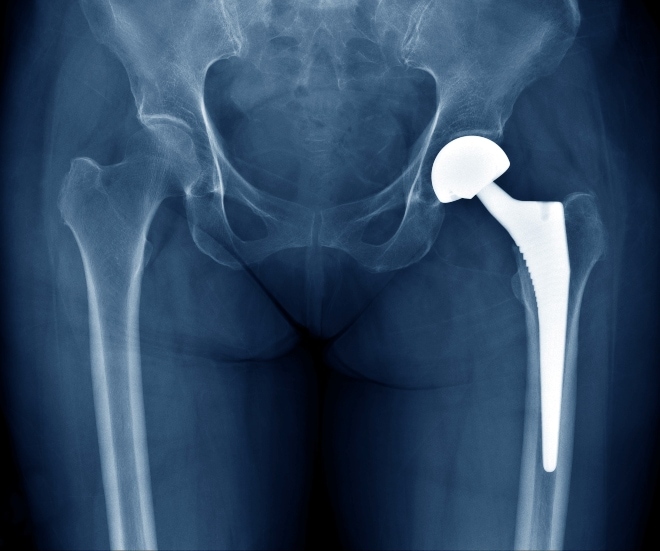

Het plaatsen van een heupprothese (heupartroplastiek) is een veelvoorkomende en vaak succesvolle procedure (zie kader). ‘Tegenwoordig kan het vervangen van een heupgewricht plaatsvinden tijdens een korte opname van 1 tot 2 dagen en soms zelfs tijdens een dagopname’, vertelt Keetie Kremers-van de Hei, verpleegkundig specialist orthopedie/traumatologie in het CWZ in Nijmegen. ‘Dit fast-trackprogramma heeft de voorkeur bij vrijwel alle patiënten.’

In bijna alle gevallen gaat het om een totale heupprothese (THP): het vervangen van zowel de kop als de kom. Bij een fractuur waarbij alleen de kop is gebroken (mediale collumfractuur) en er dus alleen schade is aan het femorale deel van het heupgewricht wordt een kophalsprothese (hemiprothese) geplaatst. In dit artikel richten we ons op de THP.

De metalen die gebruikt worden voor een THP zijn al lange tijd hetzelfde. De meeste stelen en kommen worden gemaakt van titanium of een kobalt-chroomlegering.2

Gecementeerd versus ongecementeerd

Er bestaan 2 methoden om een heupprothese in het bot vast te zetten: gecementeerde en ongecementeerde fixatie. Bij de gecementeerde methode wordt de prothese in het bot gefixeerd met botcement, terwijl de prothese bij de ongecementeerde methode klemvast in het bot wordt geplaatst. Stelen en kommen die ongecementeerd vastgezet worden, hebben vaak een coating die de botingroei bevordert. Op dit moment is 67% van de THP’s ongecementeerd, 24% gecementeerd en bij de resterende 9% is een hybride fixatie toegepast, dat wil zeggen dat de steel gecementeerd is en de kom ongecementeerd, of andersom.3 De fixatiemethode maakt geen verschil voor de revalidatie of voor het dagelijks leven van de patiënt.

Er is nog geen duidelijkheid over wat de beste methode is. Bij jongere patiënten (<55 jaar) wordt steeds vaker de ongecementeerde methode gebruikt. Reden hiervoor is dat een heupprothese gemiddeld 15 jaar meegaat en dus bij jongere patiënten vaak later in het leven nog eens vervangen moet worden. Bij een gecementeerde prothese gaat dat een stuk lastiger. Bij patiënten ouder dan 65 jaar blijkt een gecementeerde fixatie juist beter te werken, vooral omdat bij hen de botkwaliteit lager is en er een hoger fractuurrisico is tijdens het inbrengen van een ongecementeerde prothese.2